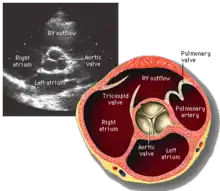

La valve aortique est située entre la chambre de chasse du ventricule gauche et l'aorte ascendante. Elle est constituée de trois cuspides semi-lunaires. Les cuspides sont des replis d'endocarde sur une lame fibreuse attachée à la paroi du ventricule gauche et de l'aorte. Les cuspides soutiennent les trois sinus de Valsalva, qui sont trois renflements de la partie initiale de l'aorte, desquels naissent les deux artères coronaires.

L'échocardiographie permet de visualiser la valve aortique, d'étudier sa morphologie et son fonctionnement.